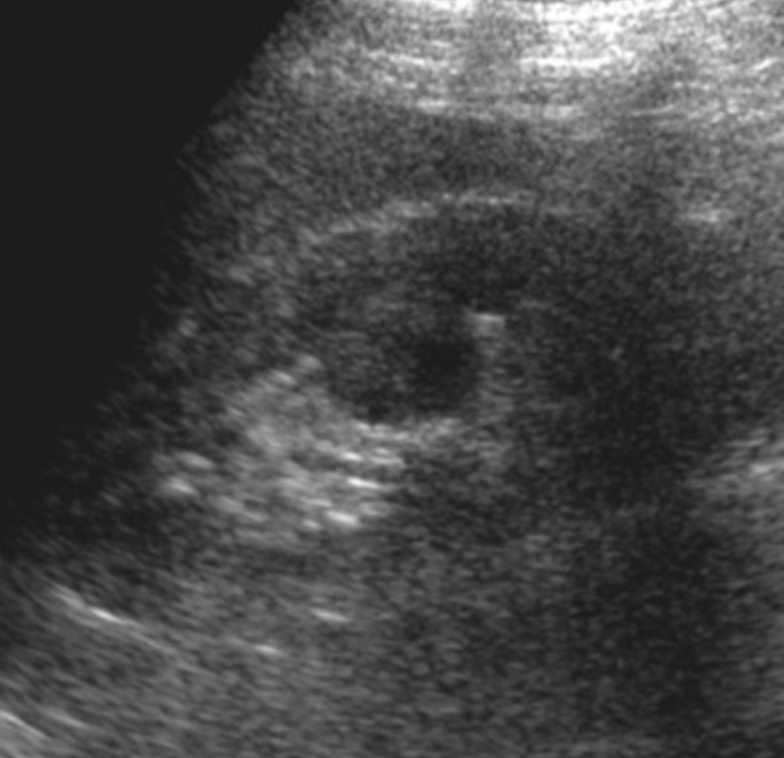

Hypertrophy of Column of Bertin

• Refers to enlarged piece of renal cortex that protrudes through the medulla

• Commonly mistaken for a renal mass

• Isoechoic/Isointense/Isodense to renal cortex

• Will show communication with the regular peripheral renal cortex

• Usually unilateral and on the left